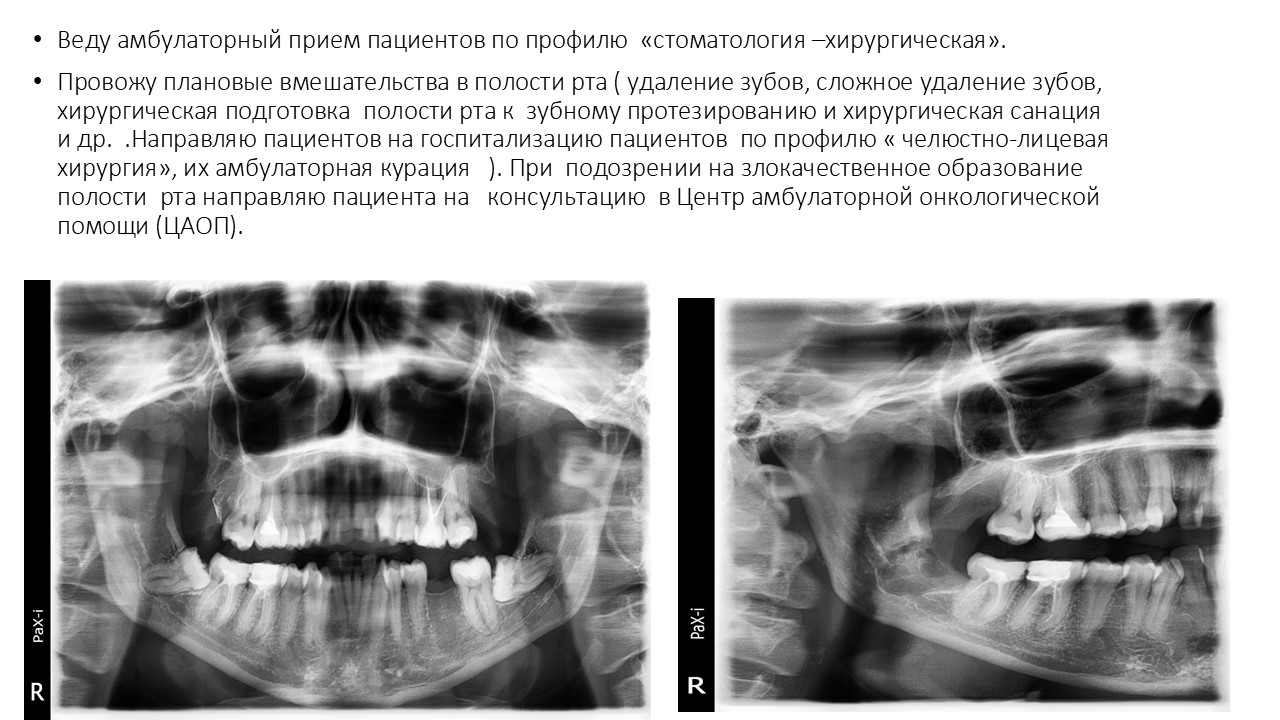

Презентация достижений (загрузите до 10 слайдов отдельными изображениями в формате .jpg)